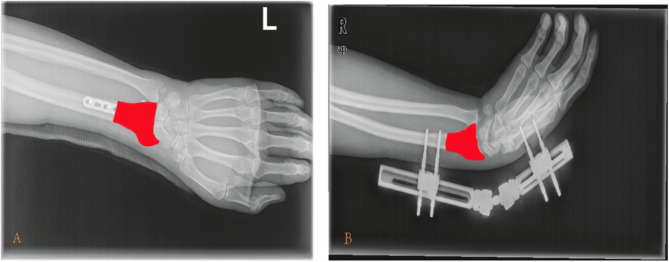

Methods: In this study, we reviewed 385 patients who underwent internal fixation with a palmar plate or external fixation bracket fixation in 2018-2020. After one year of postoperative follow-up, 169 patients completed the patient wrist evaluation (PRWE), EuroQol5D (EQ-5D), and forgotten joint score-12 (FJS-12) questionnaires and were subjected to X-ray capture. The region of interest (ROI) of postoperative X-rays was outlined using 3D Slicer, and the training and test sets were divided based on the satisfaction of the patients. Python was used to extract 848 image features, and random forest embedding was used to reduce feature dimensionality. Also, a machine learning model combining the patient's functional rating scale with the downscaled X-ray-related image features was built, followed by hyperparameter debugging using the grid search method during the modeling process. The stability of the Radiomics and Integrated models was first verified using the five-fold cross-validation method, and then receiver operating characteristic curves, calibration curves, and decision curve analysis were used to evaluate the performance of the model on the training and test sets.